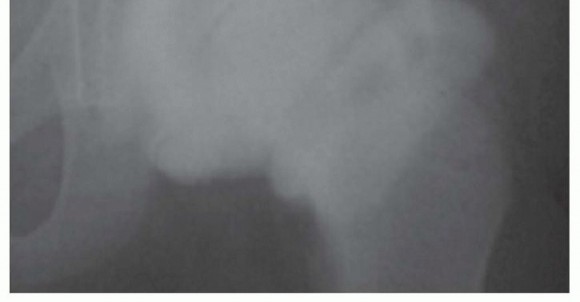

FIG 4 • Anteroposterior (AP) radiographs of the hip of a patient with Perthes disease in whom the deformed femoral head was treated by a labral support (shelf) procedure. There is remodeling of the femoral epiphysis, widening of the acetabulum, and resolution of the shelf.

*

Domzalski et al6 reported the results of 49 consecutive patients treated by the labral support (shelf) procedure for Perthes disease.

The procedure has a combined effect to prevent subluxation, to stimulate additional growth of the lateral rim of the acetabulum in a vertical dimension, and to provide temporary osseous containment until the shelf resorbs with time in a manner that is beneficial for preventing impingement of the femoral neck and greater trochanter on the shelf (

FIG 4

).